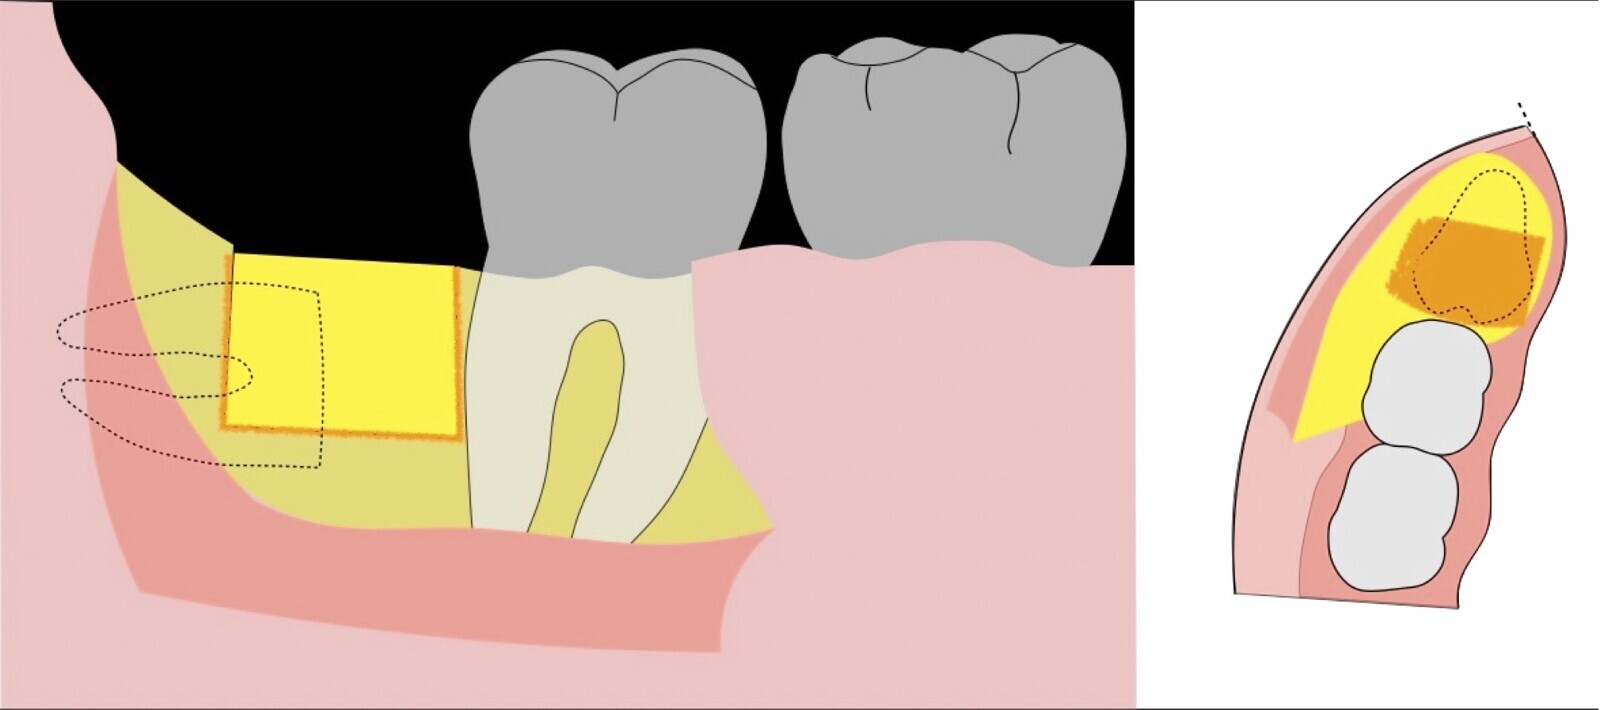

Figura 6. Demarcación y fractura de la zona de osteotomía a nivel vestibular con inserto aserrado recto y/o angulado.

Figura 7. Eliminación del fragmento vestibular.

Figura 8. Odontosección mediante fresa de alta rotación y/o inserto de corte de piezoeléctrico. Posteriormente se procede al ensanchamiento del espacio pericoronario con el periótomo de piezoeléctrico para facilitar la avulsión de la pieza dentaria.

Figura 9. Avulsión de la parte coronaria de la tercera molar.